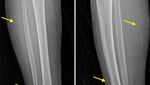

Jakarta - Belum lama ini heboh gambar rontgen penemuan benang 'susuk' emas di dalam tubuh seorang pasien di Korea Selatan. Ternyata, ini bukan kejadian yang pertama.